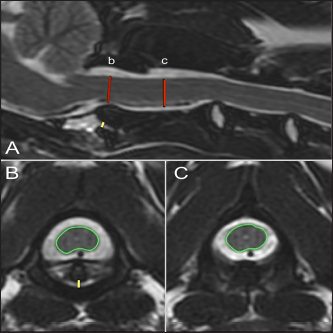

MRI characteristics were evaluated categorically and numerically. To evaluate spinal cord compression, a cross-sectional percentage of the spinal cord was calculated by outlining the spinal cord diameter at the level of the dens compared to its size at the level of the mid-body of C2 on the imaging software program (Figs. 1B and C and 2B and C). The degree of AA joint subluxation was identified as the size of the AA joint cavity, using a sagittal measurement of the distance from the ventral border of the dens or the most rostral portion of C2 to the caudal articular fovea of the atlas (Figs. 1A and 2A), and a transverse measurement from the ventral border of the dens or rostral C2 to the dorsal margin of the atlas (Figs. 1B and 2B). The integrity of apical, alar, and transverse ligaments was assessed as present (Fig. 2B), absent, or inconclusive based on the previous protocol established by Middleton et al. (2012).

Fig. 2. T2-weighted sagittal (A) and transverse (B, C) images of a 4-year-old spayed female Maltese used as a control dog (TE, 120 ms; TR, 3800 ms; slice thickness, 2.5 mm). On the sagittal image (A), the dorsoventral diameter of the spinal cord at the level of the dens (b) and mid-body of C2 (c) has been measured (red lines), as has the distance from the ventral border of the dens to the caudal articular fovea of the atlas (yellow line). On the transverse images, the cross-sectional area of the spinal cord at the level of the dens (B) and mid-body of C2 (C) has been outlined, as has the subluxation distance from the dens to the atlas (yellow line in B).